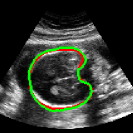

To quantitatively compare our network to the only other brain extraction method for fetal 3D US, the out test dataset was analysed with the method described in Namburete et al., 2018 [8]. The same experiments were performed and the results are shown in Table 3. Our network manages considerably better results throughout all comparisons. This is expected, since the other method relies on an approximation of the brain volume as ellipsoid, which does not accurately represent its shape. While an ellipsoid would be expected to have a high SC, its fitting to the probability mask results in an inaccurate alignment, which is reflected in the low SC of 0.74, compared to our network’s 0.95. This can be clearly seen in Fig. 7, where a comparison of their method with ours is shown.

| Original | Namb. 01 | Namb. 02 | Our work |